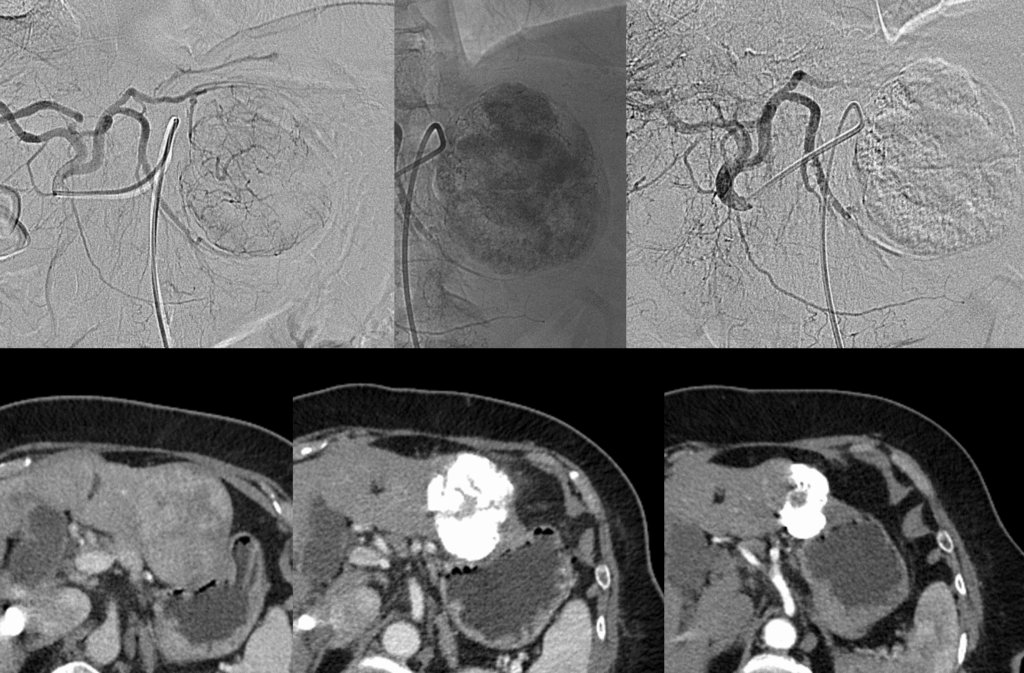

TACE is a specialized, minimally invasive procedure most commonly used to treat liver cancer (Hepatocellular Carcinoma, or HCC). It is performed by an Interventional Radiologist and combines two powerful treatments: targeted chemotherapy delivery and vessel embolization (blocking).